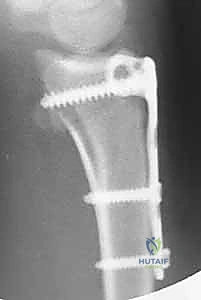

خطوات العملية الجراحية مع الأستاذ الدكتور محمد هطيف

تُجرى عملية تثبيت كسر الكعبرة البعيدة بالشريحة الظهرية في مستشفيات صنعاء المجهزة بأحدث التقنيات تحت إشراف مباشر من أ.د. محمد هطيف. تمر العملية بخطوات دقيقة ومدروسة:

4. وضع الشريحة والتثبيت بالمسامير

بمجرد أن يصبح العظم في موضعه الصحيح، يتم وضع الش